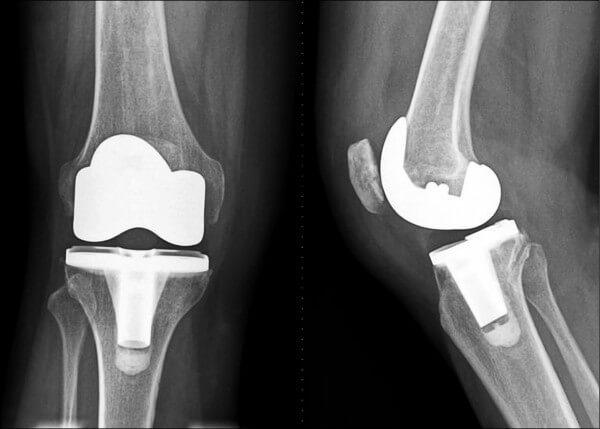

前十字韧带(ACL)撕裂几乎是篮球运动员最怕听到的词。它往往发生在落地不稳或急停转向时,一旦撕裂,至少需要6-9个月才能重返赛场。

AG官网在一篇专题中提到,现代康复训练强调“神经肌肉控制”,通过核心力量与平衡训练降低受伤几率。这种理念已逐渐被职业球队采纳。